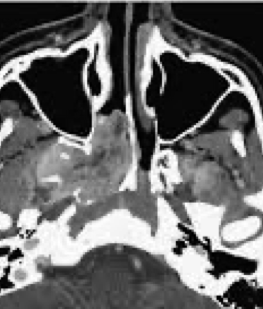

• Imaging: CT and MRI

• Angiography: Carotid angiography and MR angiography show feeding vessel of the tumor and allow preoperative embolization to minimize intraoperative bleeding.